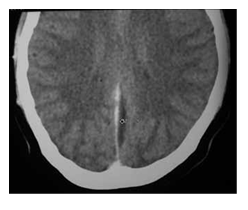

Imaging is required to rule out concomitant intracranial complications, or evidence of increased intracranial pressure. CT scan may show ventricular dilatation (Figure 10). In cases of otitic hydrocephalus, an MRI and magnetic resonance venogram should be performed to evaluate for ventricular enlargement, or coexisting intracranial complications, such as significant sinus thrombosis with obstruction. Magnetic resonance venogram will also confirm the presence of lateral sinus thrombosis, but is not required to make a diagnosis of otitic hydrocephalus.

Figure 10 CT scan showing dilated ventricles.